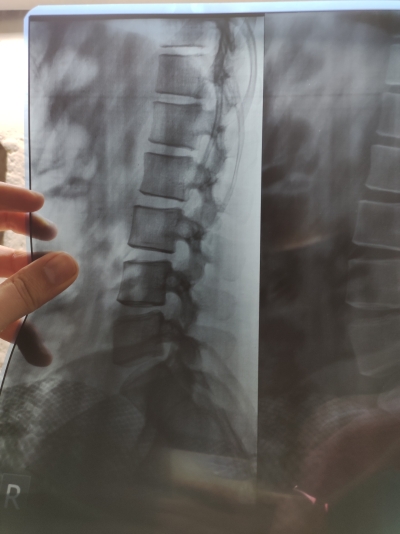

انزلاق في الفقرة الخامسة والعجزية

المرفقات

• IMG_٢٠٢٢٠٤١٦_١٩٠٤٢٢.jpg

IMG_٢٠٢٢٠٤١٦_١٩٠٤٢٢.jpg

106.4 KB · المشاهدات: 1,043